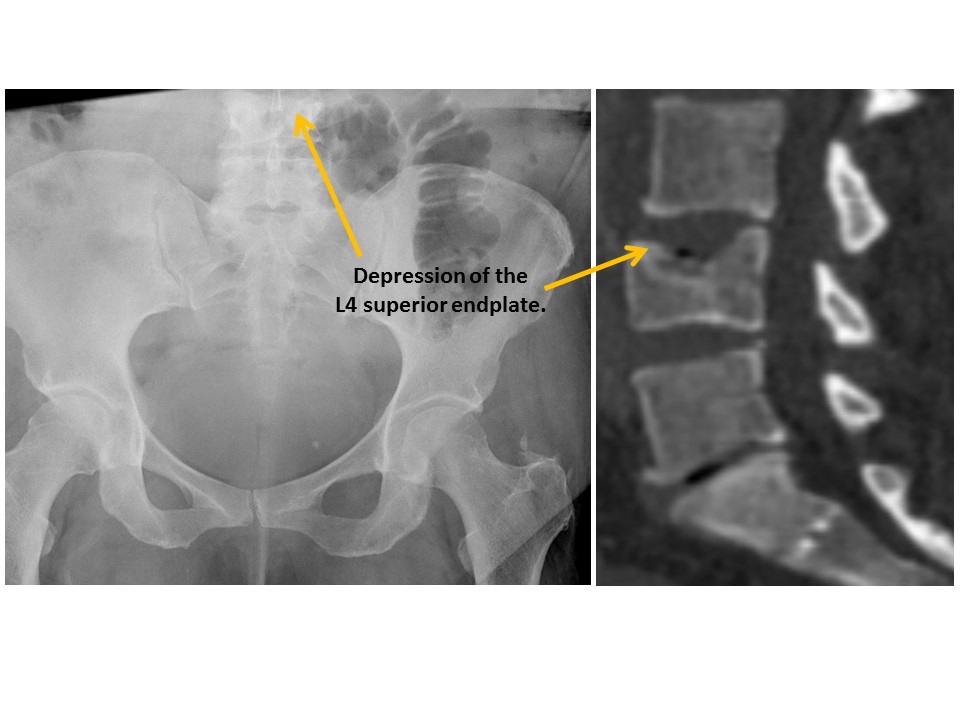

VISUALIZED LUMBAR SPINE

There are compression fractures. [Yes/No]

There are transverse process fractures. [Yes/No]

There is lumbar spine degeneration. [Yes/No]